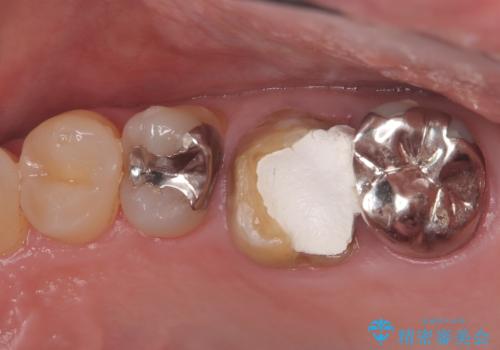

- 患者様は、他院で根管治療を受けていたが、なかなか治らず、より精密な治療を希望して当院を受診されました。マイクロスコープを使用して詳しく診断したところ、上顎第一大臼歯(6番)のMB2(第二頬側根管)の見落としが判明。このままでは感染が残り、再発のリスクが高い状態であるため、当院で精密根管治療を行う方針としました。

マイクロスコープを使用してMB2を確認し、感染源を徹底的に除去。その後、根管内を清掃・消毒し、高品質な充填材で密閉しました。従来の根管治療では見落とされがちなMB2の発見により、治療の精度が大幅に向上し、炎症の改善が期待できる状態となりました。患者様からは「治療後の違和感がなくなり、しっかり噛めるようになった」と喜びの声をいただきました。